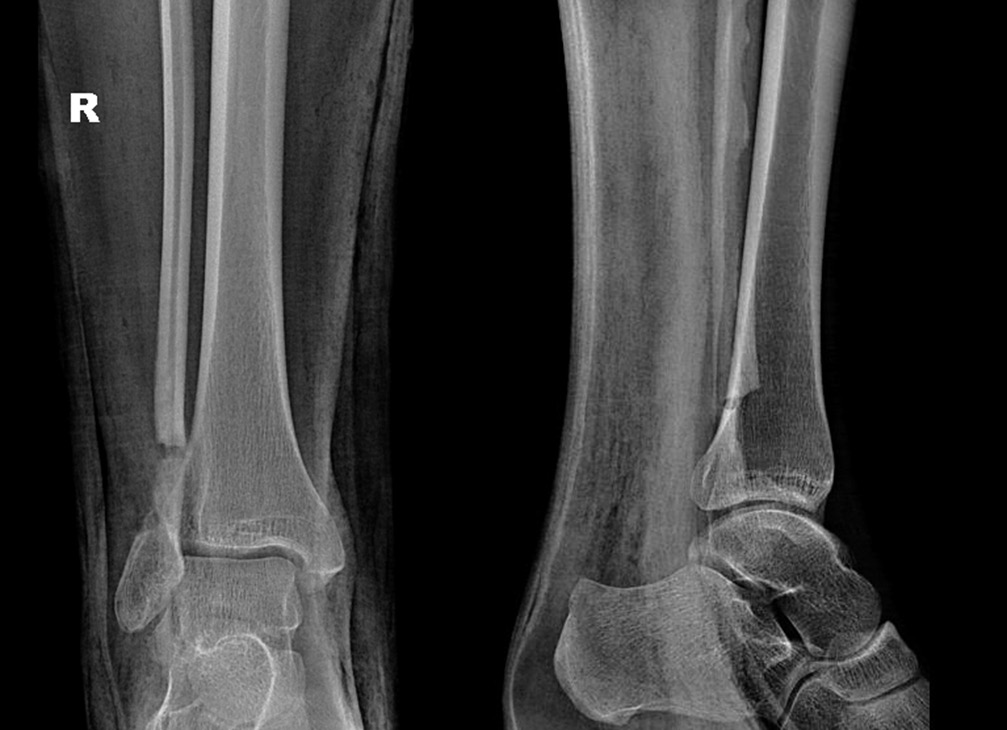

После получения травмы голеностопного сустава у 13-летней пациентки при рентгенологическом обследовании обнаружен очаг деструкции нижней трети правой малоберцовой кости овальной формы размером 1,9 × 0,8 см (30.11.2012) (рис. 1). Был рекомендован рентгенологический контроль через каждые 6 мес. Спустя год на снимке определялось увеличение размеров полости до 2,2 × 1,0 см. Пациентка жаловалась на непостоянный болевой синдром слабой выраженности (по визуальной аналоговой шкале (ВАШ) 2–3 балла), усиливающийся при физических нагрузках (по ВАШ до 5–6 баллов).

Рис. 1. Рентгенограмма. В проекции нижней трети правой малоберцовой кости кистозное образование овальной формы с четкими, ровными контурами, размером 1,9 × 0,8 см, кортикальный слой на уровне образования истончен